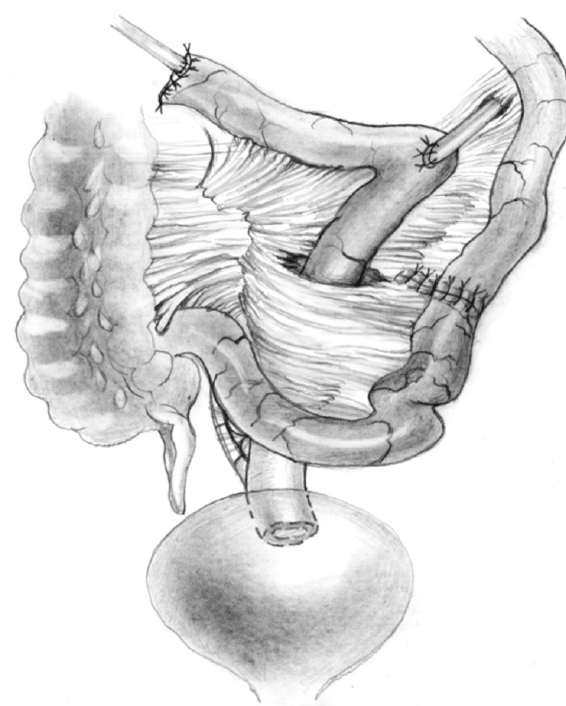

Bilateral small intestinal reconstruction of the ureters was performed in 40 (20.7%) patients. Most often, in 24 (60.0%) patients, U-shaped ileoureteroplasty was performed (Figs. 8 and 9), and more complex reconstructions were performed less often; that is, Y-shaped in 1 (2.5%) case, J-shaped in 3 (7.5%), L- and 7-shaped (Figs. 10 and 11) ileoureteroplasty in 6 (15.0%), and that with two separate ileografts in 6 (15.0%) cases.

Fig. 10. Bilateral isoperistaltic 7-shaped ileoureteroplasty

Bilateral ileoureteroplasty is a more complex and traumatic surgical procedure. Most often, the need for the procedure arises in case of radiation damage to the urinary tract. Partial or complete replacement of both ureters can be performed simultaneously or in stages using one or two separate segments of the bowel. The staged approach to surgery depends on the severity of the patient’s condition and destructive changes in the urinary tract. Bilateral ileoureteroplasty becomes more complicated because the length of the ureteral sections requiring replacement increases. This is due to (1) a wide and traumatic surgical approach; (2) the need to exclude a more extended segment from the small intestine; (3) the inclusion of a long convoluted segment(s) of the intestine into the urinary system, which leads to a larger area of resorption and an increased risk of metabolic disorders; and (4) the abovementioned complicated aspects of plastic surgery of the right ureter in the isoperistaltic position.